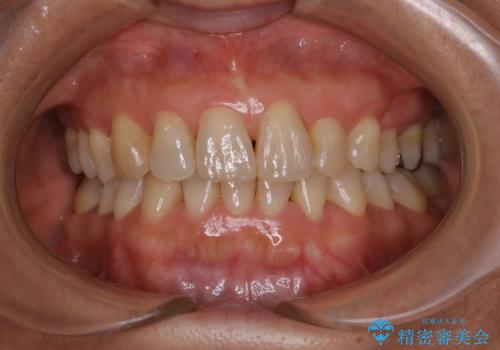

一度諦めた矯正にチャレンジしたい インビザラインとセラミック治療

少しだけ飛び出た前歯を整えたい インビザラインによる矯正治療

抜けてしまうと言われた前歯 インビザラインによる矯正治療

深いかみ合わせ 出っ歯の治療 インビザラインで

見た目だけじゃない:マウスピースでも短期間で噛み合わせと口元を改善

飛び出した前歯と黄ばんだ歯 ホワイトニングしながらマウスピース矯正

下の前歯が見えない:深い噛み合わせもインビザラインで

【モニター】前歯のデコボコをインビザラインできれいに整える

治療途中の前歯を治したい インビザライン矯正とオールセラミッククラウン

入国制限で帰国できず 海外出張中のインビザライン矯正

前歯のデコボコと突出感 インビザラインにて矯正治療

奥歯の銀歯と歯並びを改善 歯周外科治療と矯正治療を行った総合歯科診療